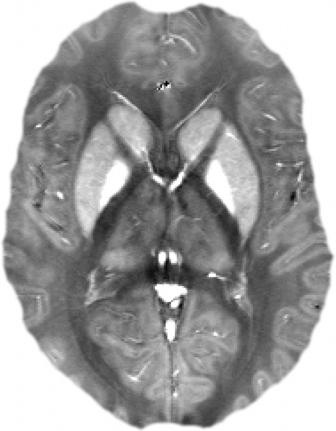

„Die magnetische Suszeptibilitätskartierung stellt hier ein neuartiges MR-tomographisches Verfahren dar, mit dessen Hilfe magnetische Gewebeeigenschaften im Gehirn auf nicht-invasive Weise abgebildet und quantifiziert werden können", so Prof. Dr. Jürgen Reichenbach. Er leitet die Arbeitsgruppe Medizinische Physik am Institut für Diagnostische und Interventionelle Radiologie I des Universitätsklinikums Jena, die zu den Pionieren dieses neuen Verfahrens gehört. Mit Hilfe der Suszeptibilitätskartierung wird die spezifische Magnetisierbarkeit des Gewebes bestimmt und anhand dreidimensionaler Bilder visualisiert. „So lassen sich beispielsweise Eisenablagerungen bei Patienten nachweisen und quantifizieren. Diese Eisenablagerungen spielen bei neurodegenerativen Erkrankungen wie Alzheimer oder Parkinson eine wichtige Rolle", beschreibt Professor Reichenbach eine mögliche Anwendung.